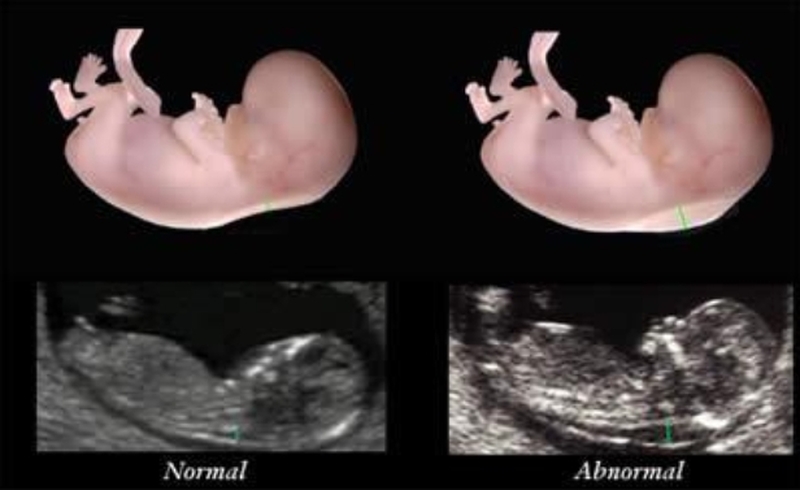

Độ mờ da gáy được biết đến là một nơi kết tụ chất dịch ở vùng da mặt sau cổ của thai nhi, qua chỉ số này, các bác sĩ sẽ đánh giá được nguy cơ mắc các hội chứng dị tật bẩm sinh ở trẻ sớm nhất.

Có một điều các cha mẹ cần lưu ý đó là tất cả thai nhi đều có độ mờ da gáy, nhưng đối với trẻ có nguy cơ cao mắc hội chứng Down hơn thì chất dịch này sẽ nhiều và dày hơn bình thường.

Ngoài ra, dựa vào độ mờ da gáy, bên cạnh bệnh Down, các bác sĩ còn phát hiện trẻ có sự bất thường về nhiễm sắc thể hay không. Những đứa trẻ khỏe mạnh sẽ có lớp dịch sau gáy mỏng và ít hơn so với đứa trẻ có nguy cơ mắc hội chứng Down.

Chỉ số độ mờ da gáy ở thai nhi càng cao thì nguy cơ mắc các dị tật bất thường càng nhiều và kèm theo các khiếm khuyết trên cơ thể, vì thế để có kết quả chính xác nhất, mẹ bầu cần thực hiện đo độ mờ da gáy đúng thời điểm.

Độ mờ da gáy 1.1 có bình thường không? Nên đo độ mờ gáy ở tuần thai thứ mấy? 2 Độ mờ da gáy càng lớn, tỷ lệ trẻ bị mắc hội chứng Down và dị tật bẩm sinh càng cao.